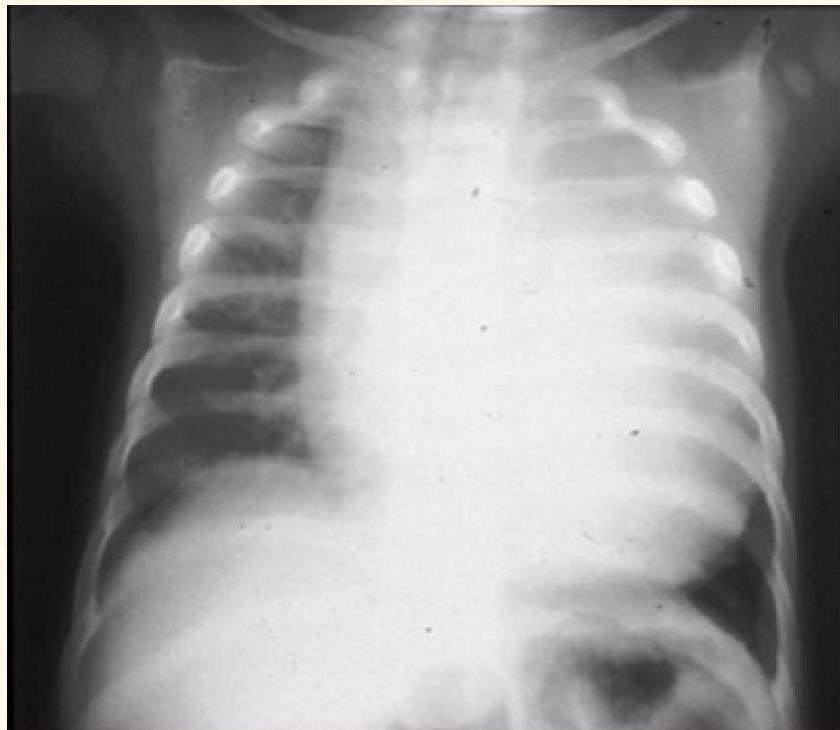

- Cardiomyopathy and severe generalized muscular hypotonia (respiratory distress, muscle weakness, feeding difficulties and failure to thrive)